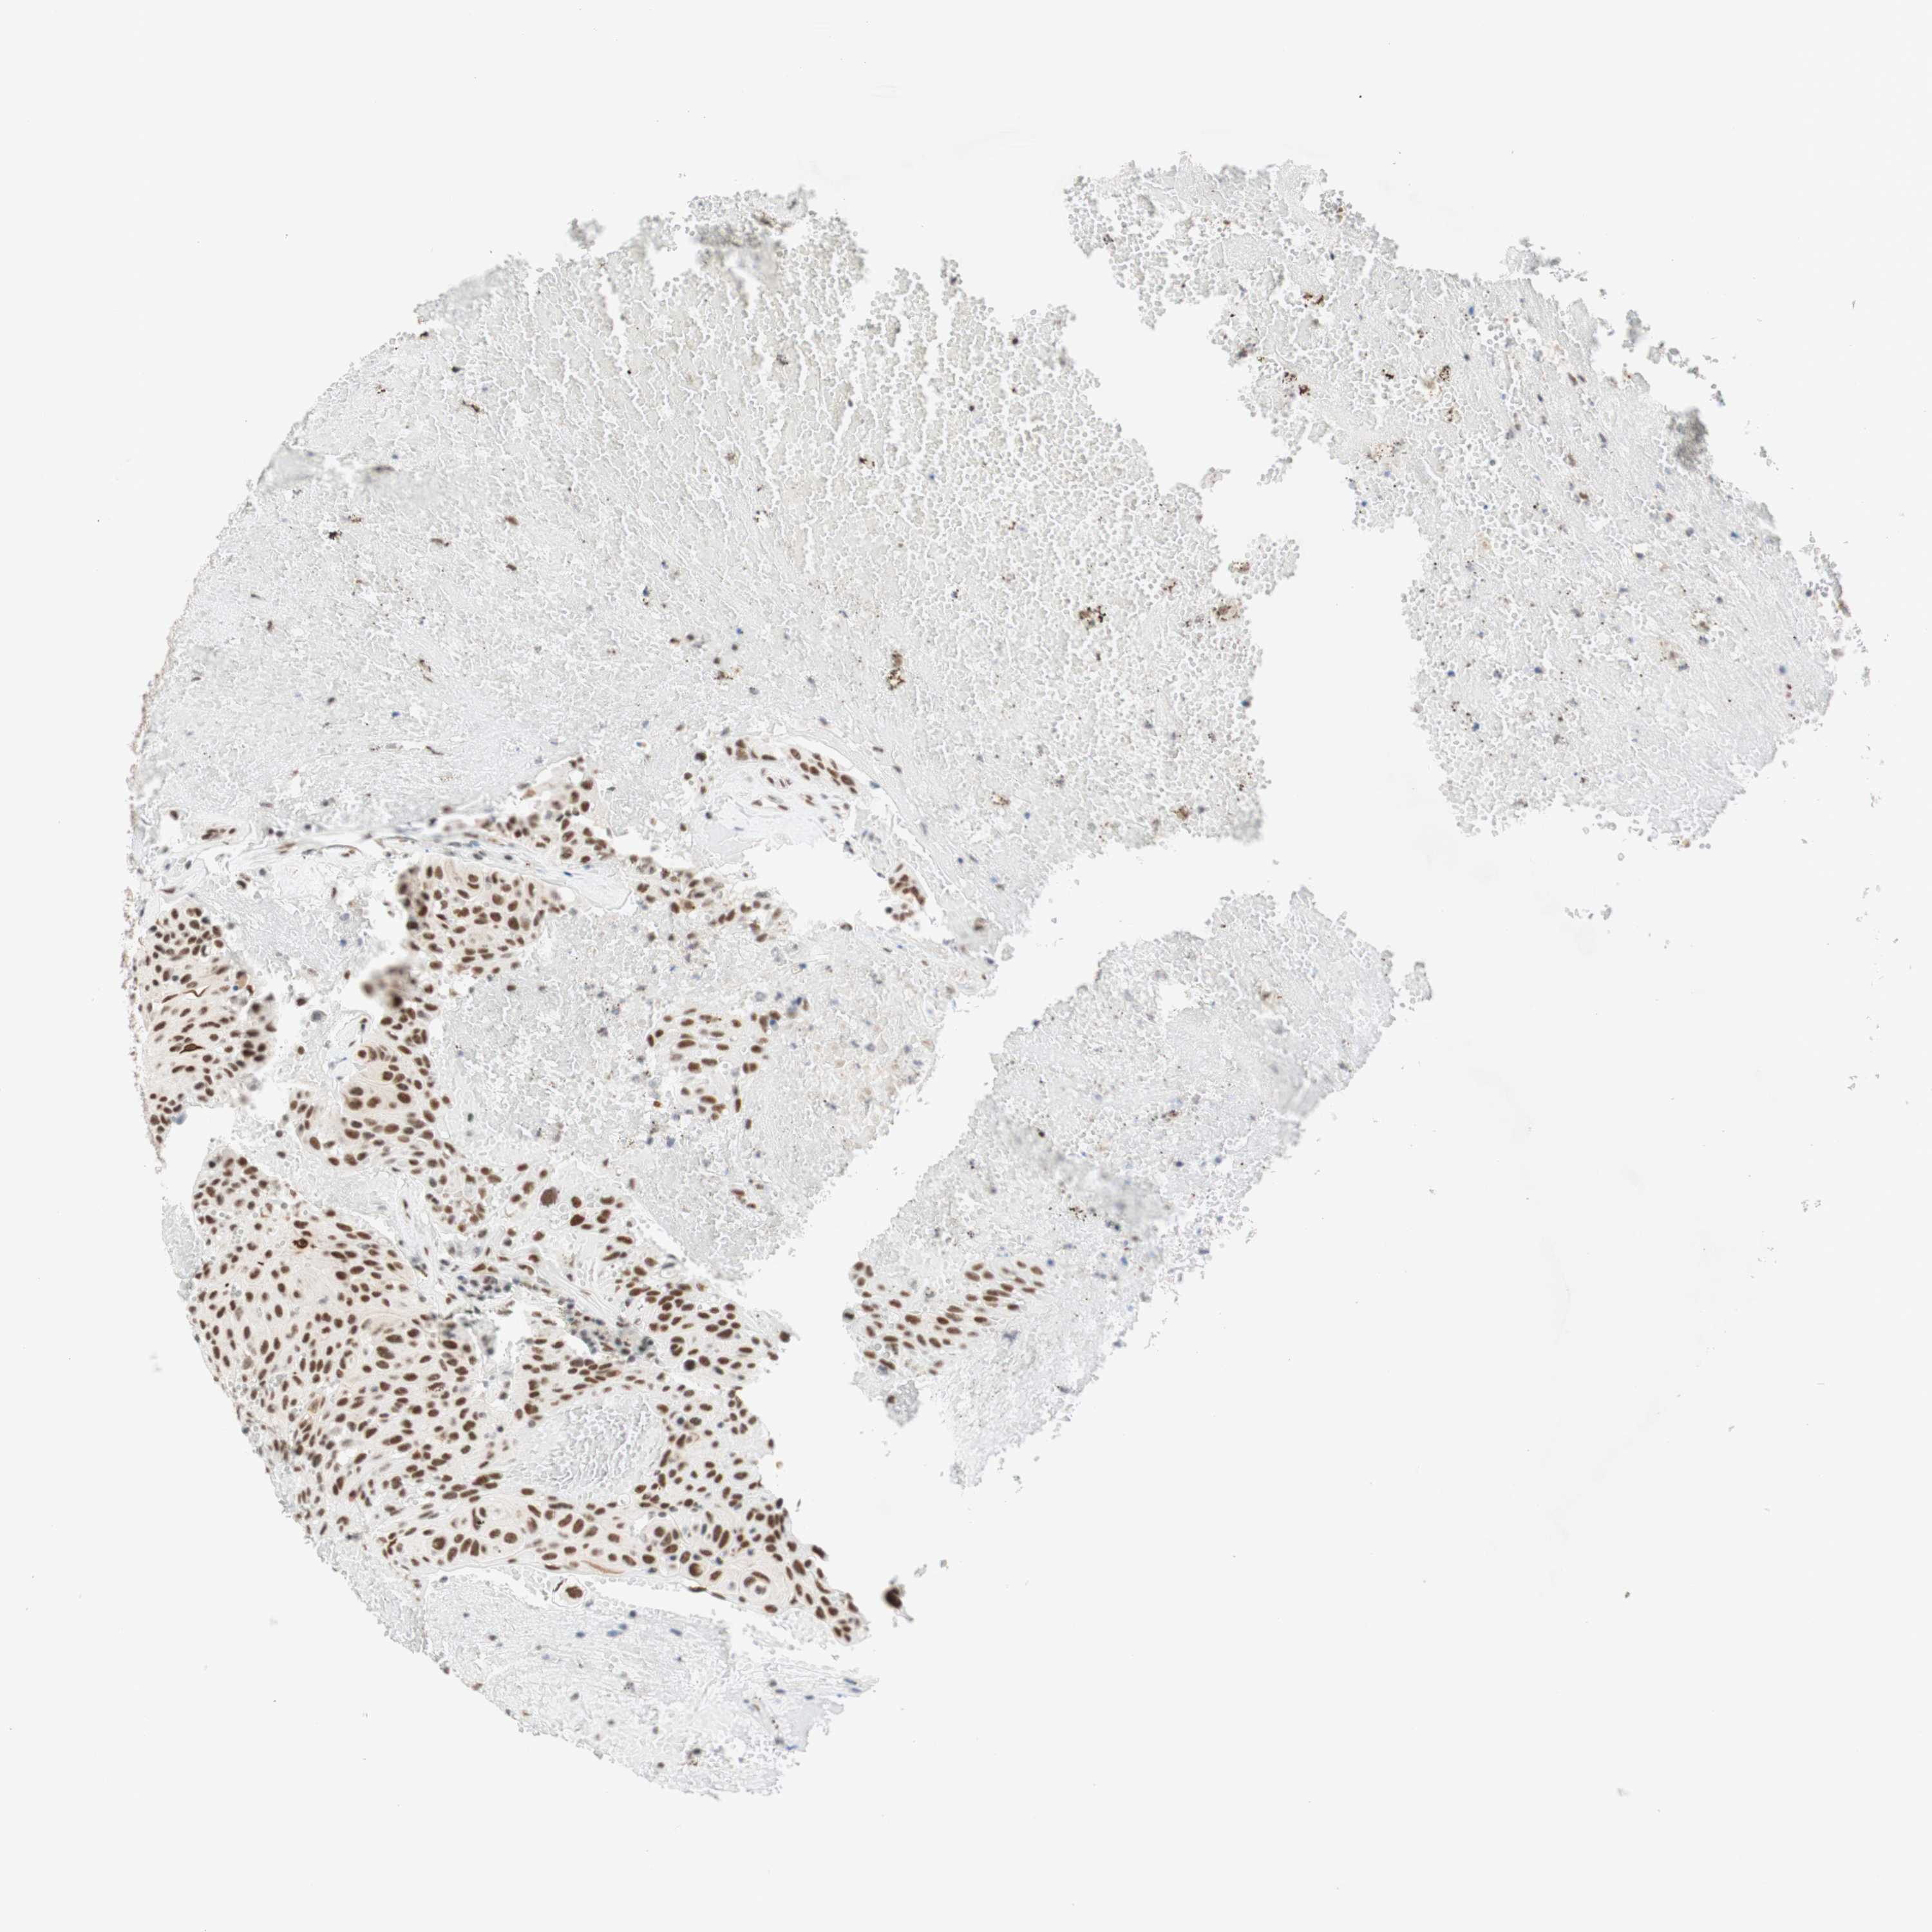

UROTHELIAL CANCER - Protein expressioni

A mouse-over function shows sample information and annotation data. Click on an image to view it in a full screen mode. Samples can be filtered based on level of antibody staining by selecting one or several of the following categories: high, medium, low and not detected. The assay and annotation is described here.

Note that samples used for immunohistochemistry by the Human Protein Atlas do not correspond to samples in the TCGA dataset.

Antibody stainingi

Antibody staining in the annotated cell types in the current human tissue is reported as not detected, low, medium, or high, based on conventional immunohistochemistry profiling in selected tissues. This score is based on the combination of the staining intensity and fraction of stained cells.

Each image is clickable and will lead to virtual microscopy that enables deeper exploration of all samples and also displays staining intensity scores, fraction scores and subcellular localization as well as patient and tissue information for each sample.

Antibody HPA038051

Antibody HPA059070

Antibody CAB012448

Staining

High

Medium

Low

Not detected

Intensity

Strong

Moderate

Weak

Negative

Quantity

>75%

75%-25%

<25%

None

Location

Nuclear

Cytoplasmic/membranous

Cytoplasmic/membranous,nuclear

Urothelial carcinoma, High grade

Urothelial carcinoma, Low grade

Urothelial carcinoma, NOS